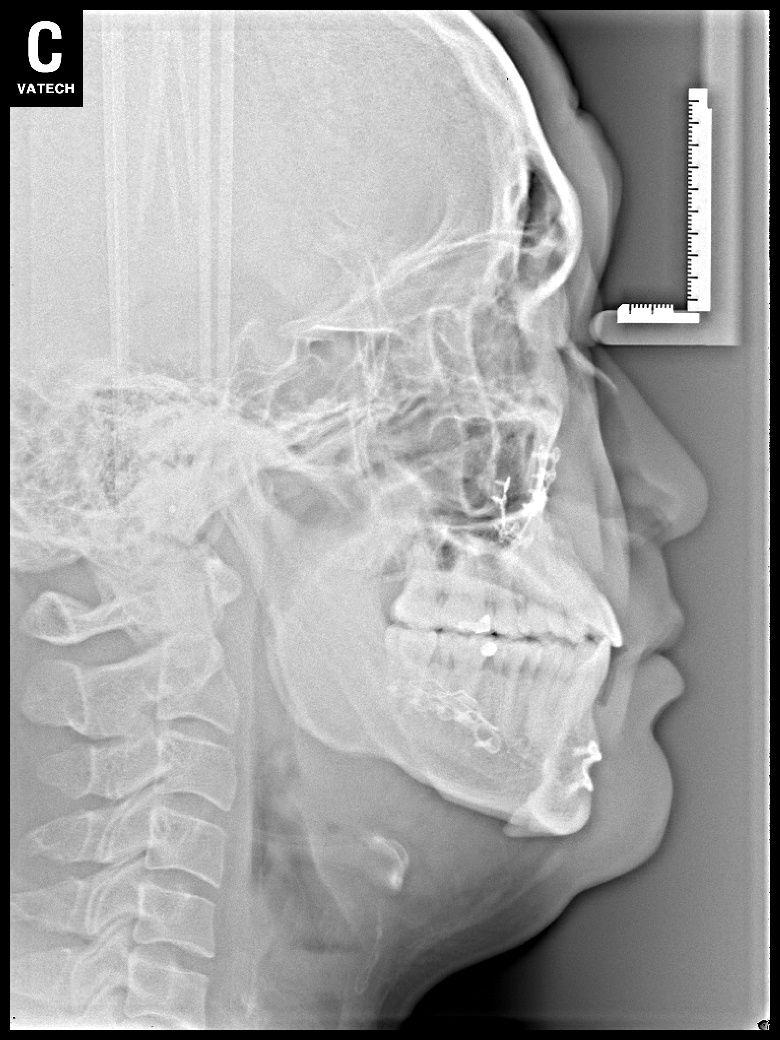

치료 후 사진입니다.